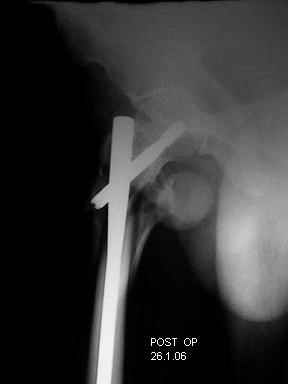

Re: Severely comminuted Trochenteric #

Few days ago I have posted an x-ray of severely comminuted Trochenteric # of Lt. Femur with sub-trochenteric extension of a male patient aged 65 years for opinion of fixation. Eight of you have kindly replied........

I choose Long Gamma Nailing and did it on 24.1.2006.

Now posting the post op x-rays for all of yours comments please. Don't hesitate to criticize me.